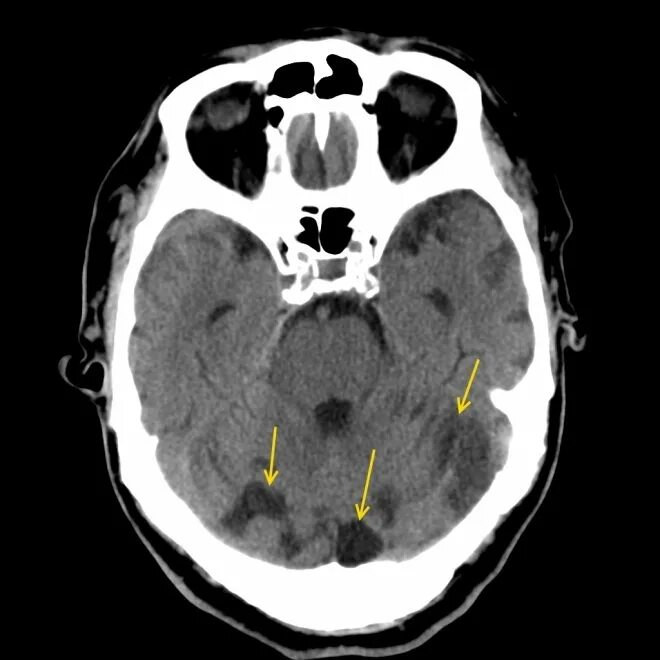

Ретроцеребеллярная ликворная киста